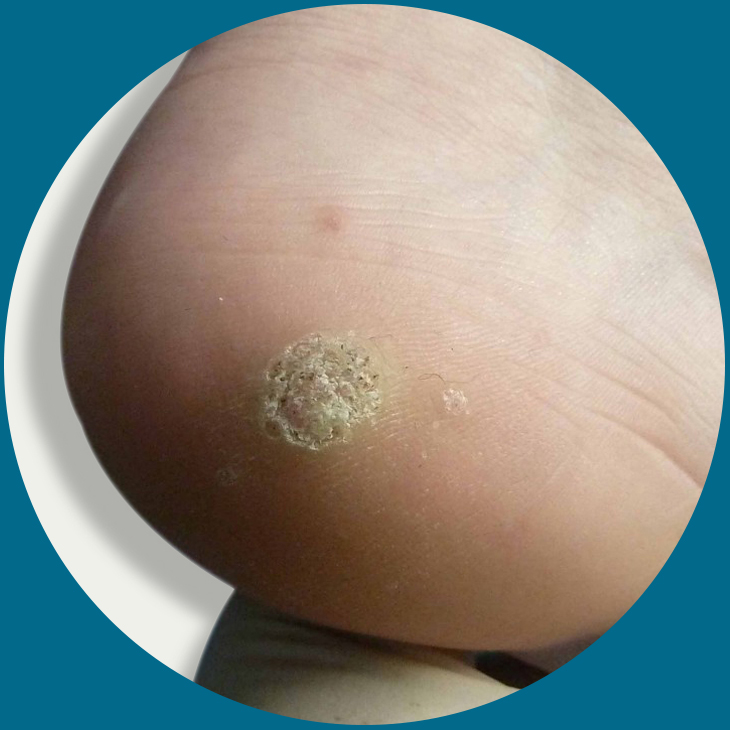

Verrucae

Verrucae are a common complaint amongst children and adults. A verruca is a small skin lesion which is commonly found on the bottom surface of the foot. The lesion is usually approximately 1cm in diameter but can be larger.

- All verrucae are caused by the human papilloma virus. This is common in all environments but does not readily attack the skin.

- If there is a break, scratch or a thorn in the skin, this will give the virus a opportunity to enter the skin.

- Verrucae are commonly contracted in communal places such as swimming pools, showers and changing areas. This is why children are more at risk of contracting verrucaes in school changing rooms and swimming pools.

- Excessive moisture or excessive dryness of the skin can lead to small crack in the skin which allows the virus to enter the skin.

Verrucae are a common complaint amongst children and adults. A verruca is a small skin lesion which is commonly found on the bottom surface of the foot. The lesion is usually approximately 1cm in diameter but can be larger.

- All verrucae are caused by the human papilloma virus. This is common in all environments but does not readily attack the skin.

- If there is a break, scratch or a thorn in the skin, this will give the virus a opportunity to enter the skin.

- Verrucae are commonly contracted in communal places such as swimming pools, showers and changing areas. This is why children are more at risk of contracting verrucaes in school changing rooms and swimming pools.

- Excessive moisture or excessive dryness of the skin can lead to small crack in the skin which allows the virus to enter the skin.